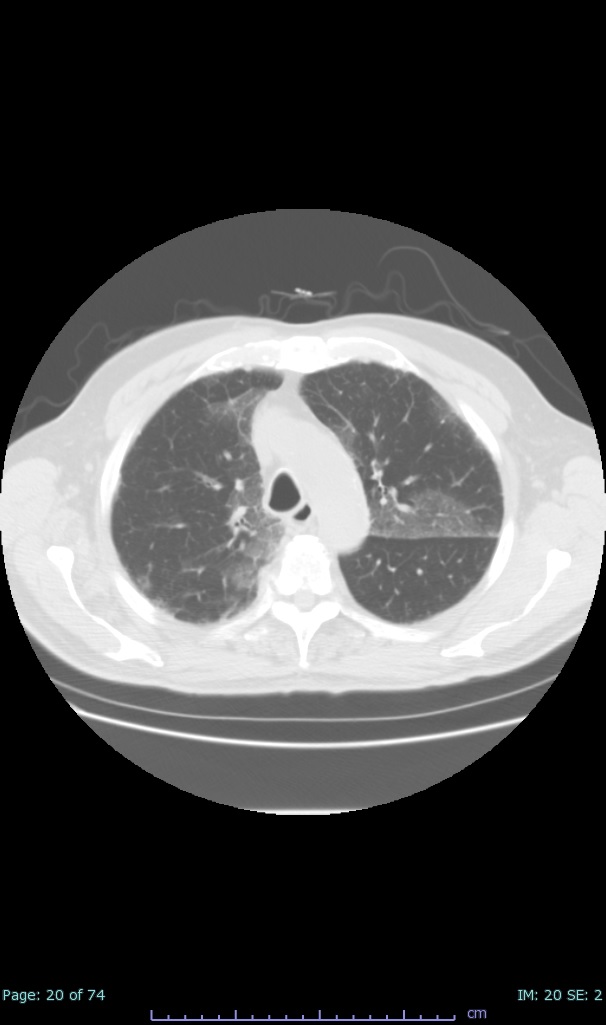

- 100% subpleural involvement, 33% + centrolobular involvement

- 40% even apical/basilar, 27% basilar dom, 5% mid dom. 1/17